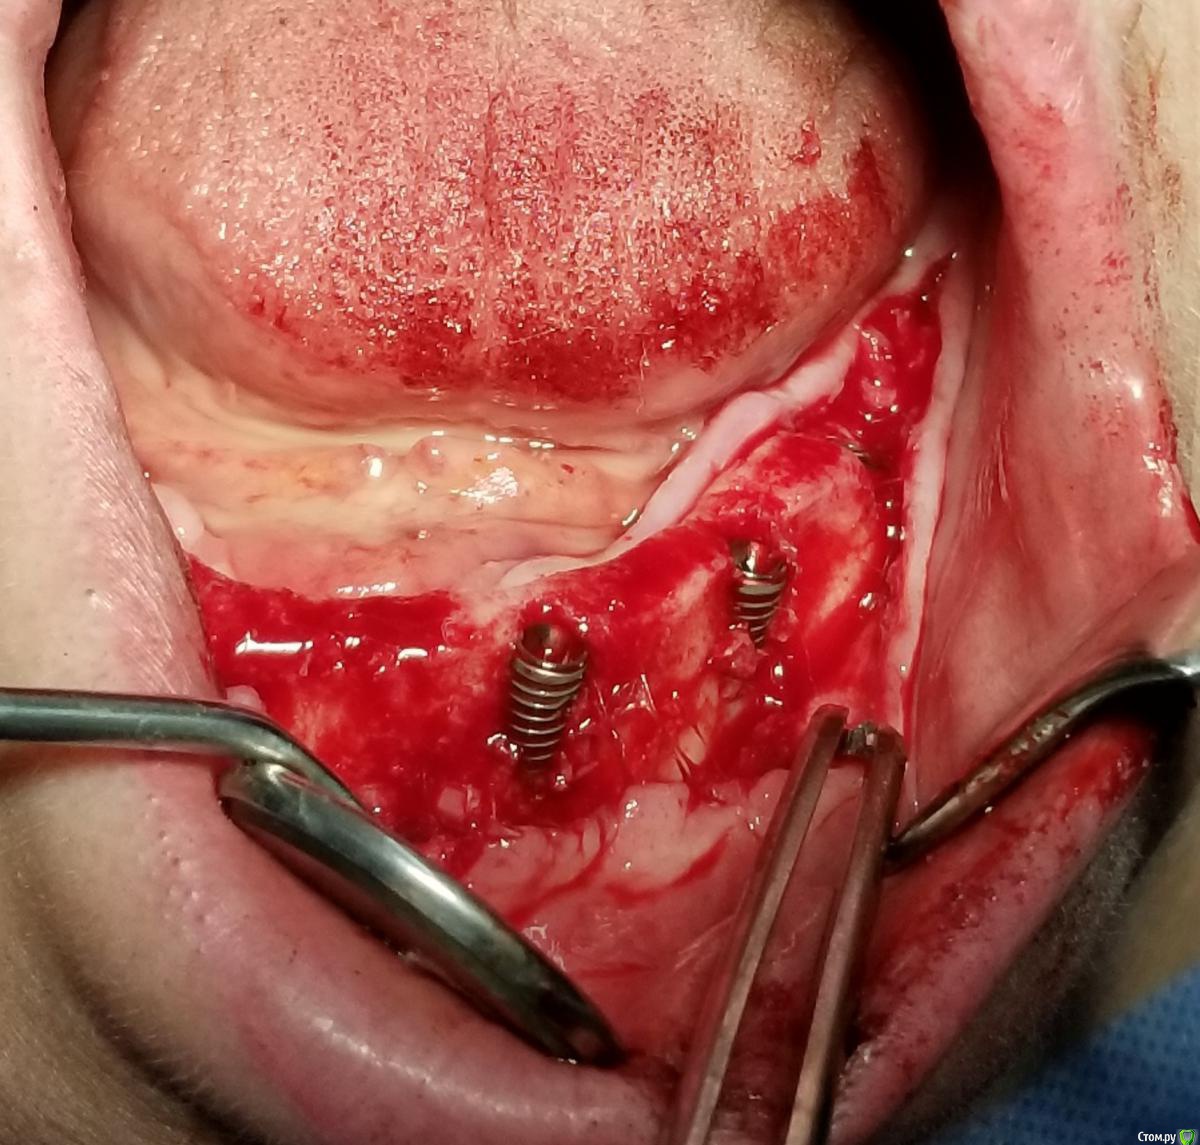

Kostoprav Опубликовано 14 июня, 2019 Поделиться Опубликовано 14 июня, 2019 Ксено+ауто +i prf, поверх титановых мембран перикард. кт через 5 мес.при и создании прикрепленки использовалась свиная дерма отечественного производителя 4 Ссылка на комментарий

Kostoprav Опубликовано 28 июня, 2019 Автор Поделиться Опубликовано 28 июня, 2019 спасибо за клинический случай! скажите,пожалуйста, это сетки,фиксированные заглушками, или смарт билдеры со спейсерами?сетки фиксировал спейсерами Ссылка на комментарий